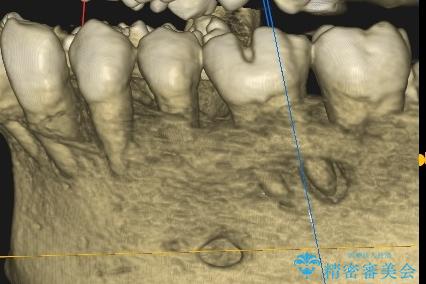

- 食事中に奥歯が痛むとのことで来院された患者様です。

レントゲンやCTより、深くまで破折していることが分かり、抜歯が必要な状態でした。

歯槽骨の状態は良好であったため、抜歯即時埋入インプラントによる補綴治療を行うこととしました。